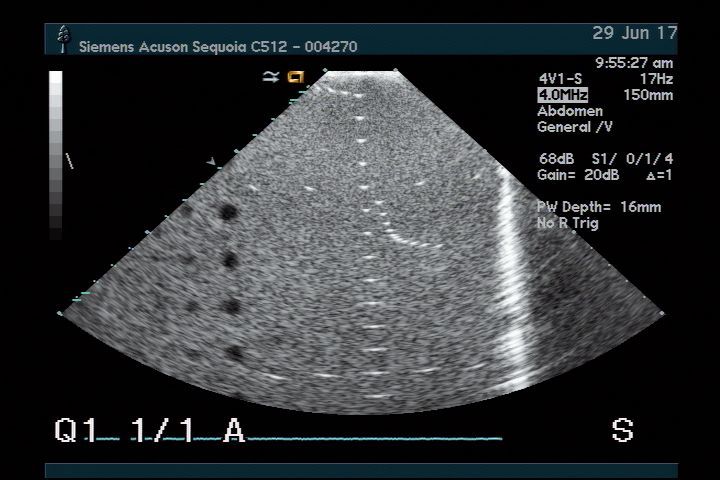

The Acuson 4V1 for Sequoia 512 Ultrasound Transducer is renowned for its superior imaging capabilities. It utilizes advanced technology to provide clear and detailed images, which are crucial for accurate diagnoses. Because of its exceptional resolution, medical professionals can identify conditions more efficiently, helping patients receive timely treatment. This transducer truly enhances diagnostic confidence.

This ultrasound transducer boasts versatility, making it suitable for various applications in healthcare. It can be used in obstetrics, cardiology, and general imaging, which means healthcare providers can rely on it for multiple patient needs. This adaptability is beneficial, as it reduces the need for multiple devices. As a result, clinics can maximize their resources effectively.